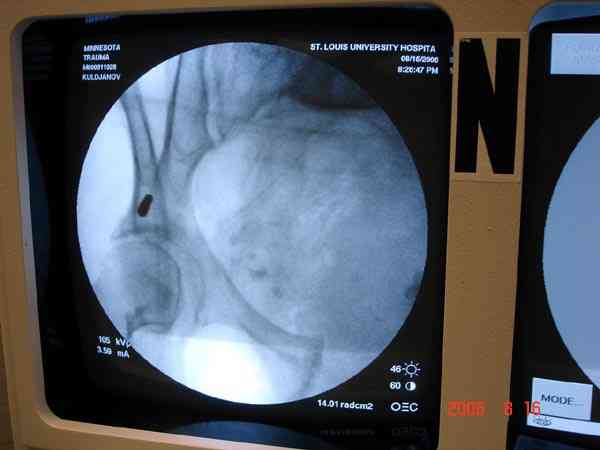

Примерно такой фиксатор наложил вчера ночью, но патология была экстренная травма: больному 53 года, поступил после мотоциклетной травмы, черепно-мозговой, абдоминальной, челюстно лицевой с потерей одного глаза, сосудистой и из скелета перелом крестца слева с диастазом симфиза и множественные переломы ребер.

Для стабилизации перелома и кровопотери, сперва была попытка наложения простыни вокруг таза для уменшения объема таза. Для оперативного доступа в области живота и передней части таза простыню заменили на Beam Bag (матрац который после удалении воздуха принимает контуры тела).

Одновременно с хирургами, которые занялись ксплоративной лапаротомией, мы приступили к фиксации временным аппаратом для уменьшения диастаза симфиза. После установки аппарата удалось стабилизировать давление, потом наше место занял сосудистый хирург, который нашел кровоточащую левую артерию epigastrica. Кровоточаший сосуд затромбизировал эндоваскулярно введением 4 coil placement.